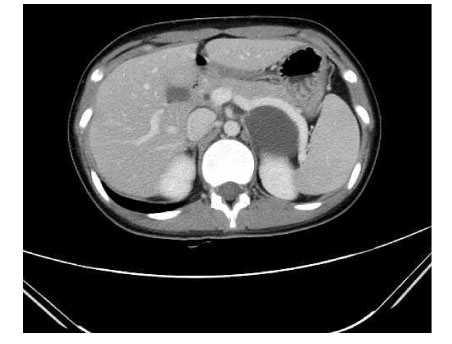

Fig. 1

Abdominal computed tomography (CT) scan revealed a cystic mass without any septum originated on the left adrenal gland.

Fig. 1 Abdominal computed tomography (CT) scan revealed a cystic mass without any septum originated on the left adrenal gland.